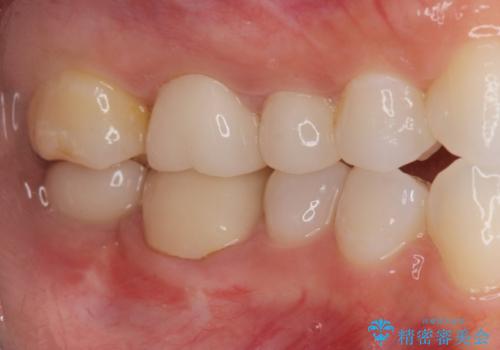

奥歯のインプラント治療

- 右下の奥歯を虫歯で喪失しそれ以来よく物が噛めず、改善を求めて来院されました。

入れ歯かインプラント治療のご提案を行い、よりしっかりとかめるインプラント治療を希望されました。

骨との結合する期間が早く、大きな咬合力にもしっかりと耐えることのできるストローマンインプラントを用いた咬合機能回復を計画します。